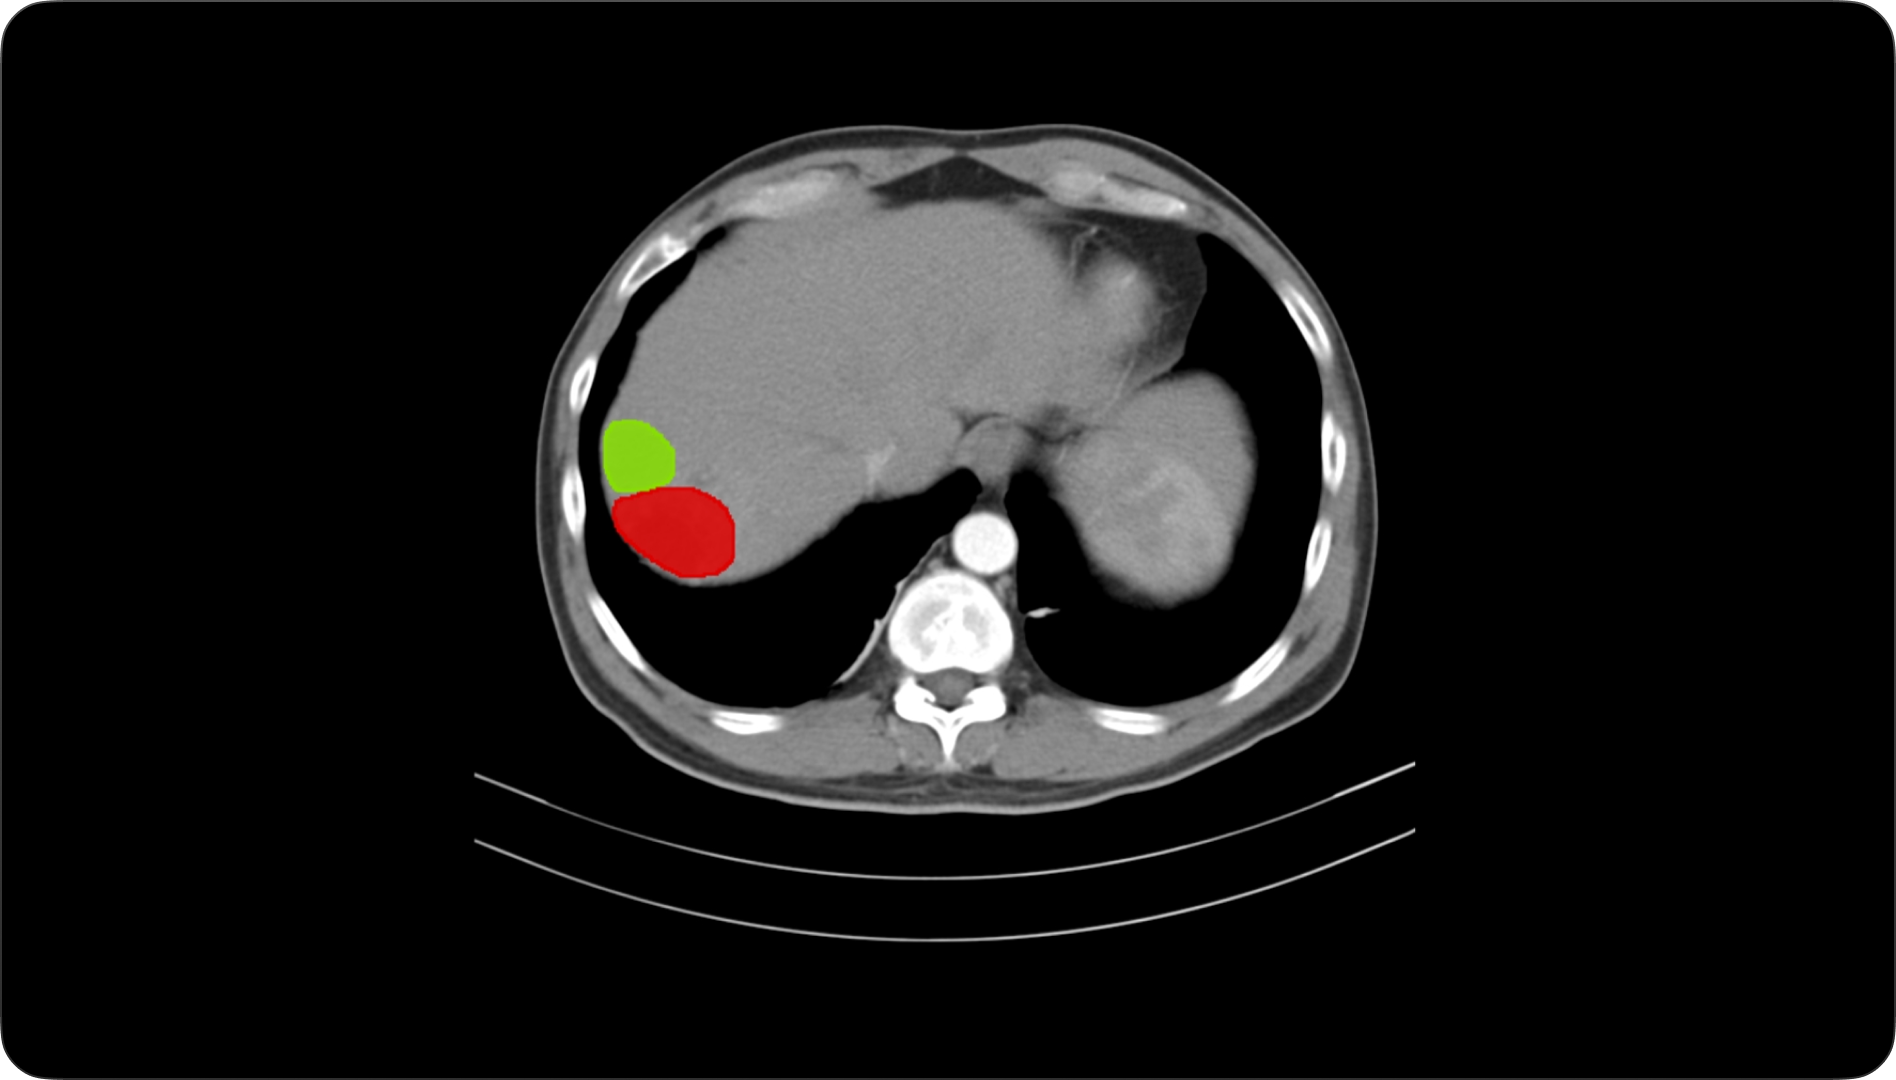

计算机视觉